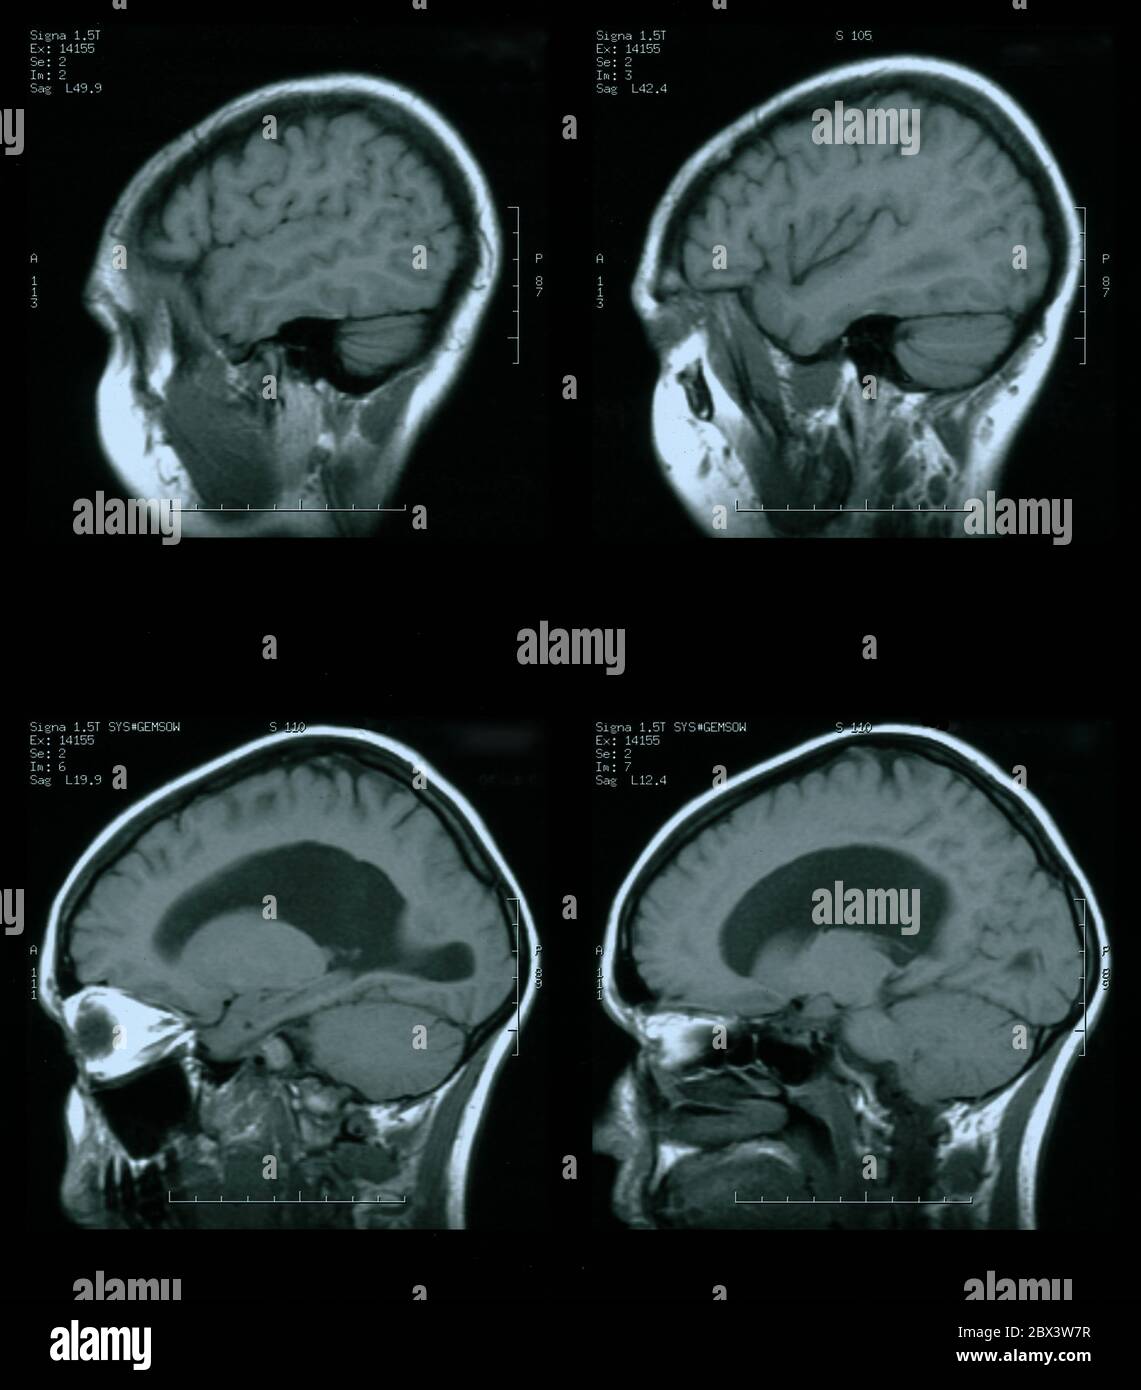

IRM du cerveau de la femme de 35 ans avec un hydrocéphalie léger Banque D'Imageshttps://www.alamyimages.fr/image-license-details/?v=1https://www.alamyimages.fr/irm-du-cerveau-de-la-femme-de-35-ans-avec-un-hydrocephalie-leger-image360274094.html

IRM du cerveau de la femme de 35 ans avec un hydrocéphalie léger Banque D'Imageshttps://www.alamyimages.fr/image-license-details/?v=1https://www.alamyimages.fr/irm-du-cerveau-de-la-femme-de-35-ans-avec-un-hydrocephalie-leger-image360274094.htmlRM2BX3W7X–IRM du cerveau de la femme de 35 ans avec un hydrocéphalie léger

IRM du cerveau de la femme de 35 ans avec un hydrocéphalie léger Banque D'Imageshttps://www.alamyimages.fr/image-license-details/?v=1https://www.alamyimages.fr/irm-du-cerveau-de-la-femme-de-35-ans-avec-un-hydrocephalie-leger-image360274091.html

IRM du cerveau de la femme de 35 ans avec un hydrocéphalie léger Banque D'Imageshttps://www.alamyimages.fr/image-license-details/?v=1https://www.alamyimages.fr/irm-du-cerveau-de-la-femme-de-35-ans-avec-un-hydrocephalie-leger-image360274091.htmlRM2BX3W7R–IRM du cerveau de la femme de 35 ans avec un hydrocéphalie léger